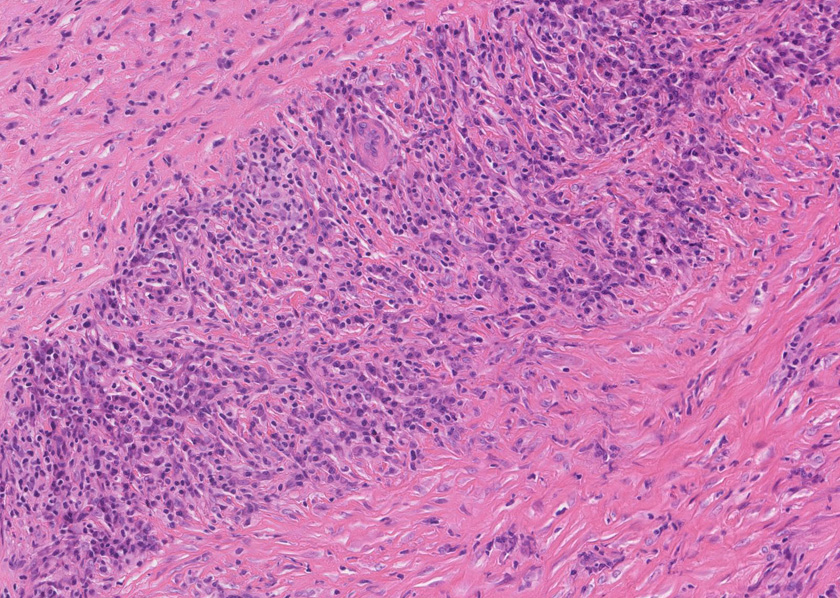

膵腺房間質にリンパ球, 形質細胞, 好中球の炎症細胞浸潤が認められる。

線維化組織に類円, 葉巻型淡明な核の紡錘型細胞が増生している。免染SMA陽性。血管周囲に慢性炎症あり。

組織像は膵腫瘤B, Cと同じくinflammatory myofibroblastic tumorである。島状に形質細胞主体の慢性炎症が強い。腹膜腫瘤には腺管は認められない。